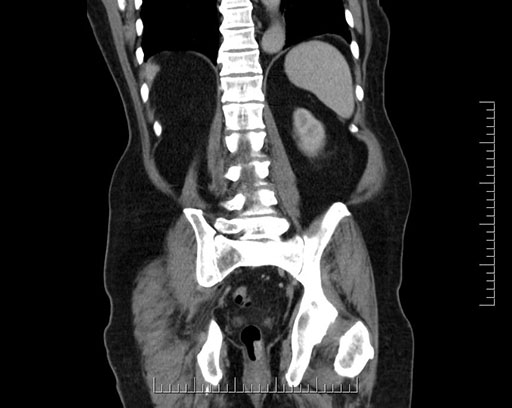

Imaging Analysis

Look through the patient's CT scan to identify any areas of concern for the necessary procedure.

Based on your CT findings, which issue(s) would give reason for "planned slowing down moment(s)" in this case?

Considering a standard Whipple procedure, what step(s) of the operation would you do differently in this case?